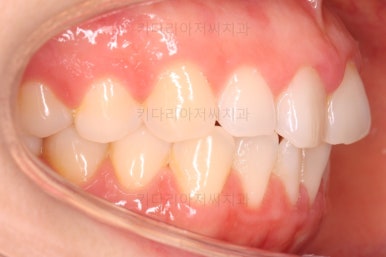

오늘 소개해 드릴 환자분은 앞니가 나비 날개처럼 꺾인 양상으로 틀어져 있었던 분으로 부분교정을 통해 개선을 하고자 하셨던 분입니다.

부산나비앞니교정 키다리아저씨치과에 처음 내원하셨을 당시의 입 안 모습입ㄴ디ㅏ.

보시다시피 위아래 정중앙에 있는 치아가 V자 형태로 꺾여있었어요.

흔히 "나비치아", "나비앞니"라고 표현을 하는데 나비 날개짓을 하듯이 꺾여 있다고 그렇게 부릅니다.

미관상 약간 보기 싫은 것도 있지만 앞니쪽이 삐뚤하게 되면 치석이 더 잘생기고 잇몸에 염증이 오기도 쉬워요.

당연히 가지런하게 해주는게 훨씬 도움이 된답니다.

어금니쪽의 맞물림은 굉장히 양호한 편이였기 때문에 부분교정에 딱 알맞는 경우였어요.